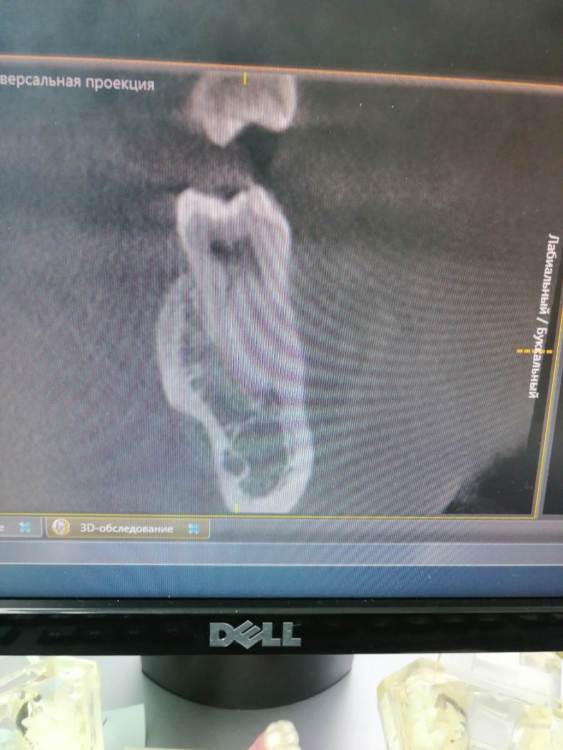

Тильда Опубликовано 30 апреля, 2021 Поделиться Опубликовано 30 апреля, 2021 (изменено) Коллеги, очень нужен ваш совет. В октябре 2020 года проведено эндо лечение 4.6 по диагноз пульпит хронический. Лечение было проведено в одно посещение, ирригант - гипохлорит, M-Two до 30 медиальные и до 40 дистальный, вертикальная конденсация. Недавно (через пол года после лечения) пациентка обратилась снова с жалобами на боли в области пролеченного ранее зуба. Причём причинный зуб локализует чётко. Боли появились сразу после лечения, постепенно немного стихли, но полностью не болит. Болит при механическом раздражение вестибулярной стенки, по словам пациентки отдаёт по челюсти. Перкуссия и термо проба безболезеннные. Слизистая без особенностей. На одном из срезов КТ можно заподозрить расширение периодонтальной щели в периапикальной области медиальных корне, но вроде бы и до лечения картина похожая. Есть ли смысл сделать повторное эндо? Буду благодарна за ваши мысли по поводу дальнейшей тактики. Извиняюсь за качество снимков и понимаю, что их сложно оценить Изменено 30 апреля, 2021 пользователем Тильда Ссылка на комментарий